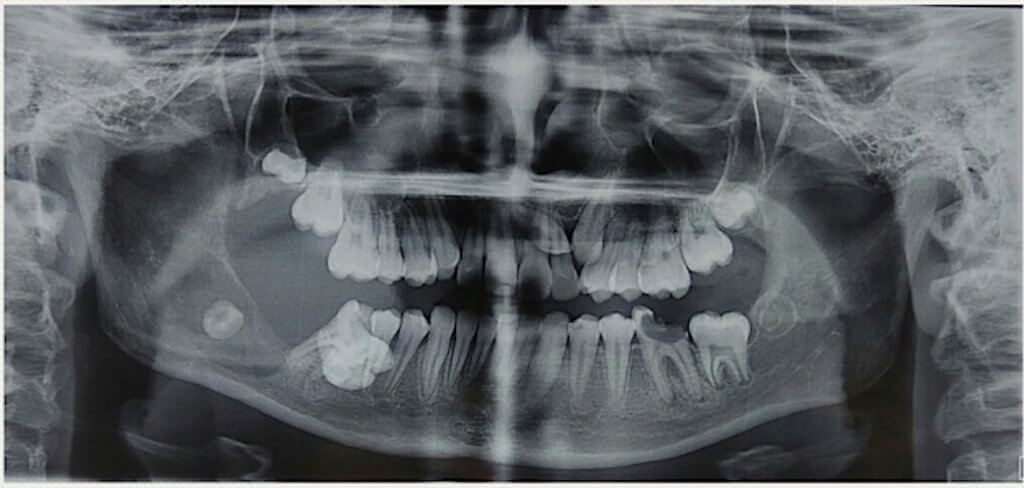

Рентгенологическая диагностика саркомы у кошек

Раздел: Визуальный дайджест